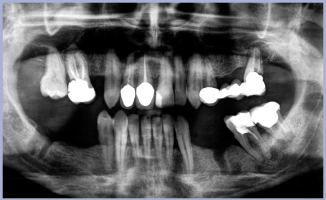

La paziente, di 54 anni, per cause familiari ha trascurato a lungo la salute dei propri denti.

Un forte dolore al 47 (poi estratto) l’ha costretta a rivolgersi all’odontoiatra convincendola ad accettare un riesame generale della bocca e a pianificare le cure indispensabili.

Dall’OPT iniziale sono risultate necessarie alcune estrazioni nell’arcata inferiore ed una conseguente riabilitazione provvisoria con protesi mobile scheletrata.

Nell’arcata superiore, in accordo con la paziente, è stata conferita priorità al settore anteriore: la corona veneer in resina presente sul 11 era da sostituire, mentre il 12 presentava una lesione periapicale di notevoli dimensioni. La protesizzazione dei due centrali e di un impianto post-estrattivo del 12 con corone integrali in ceramica su zirconia è risultata essere la terapia di prima scelta.

- OPT iniziale